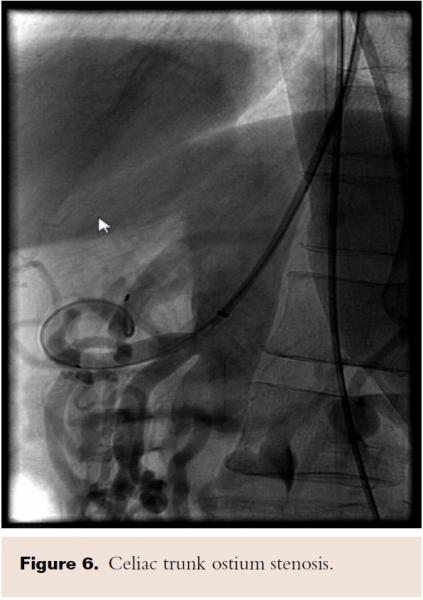

PTA of the proximal celiac trunk was performed with a 6.0 x 20 mm Mustang balloon. As expected, there was no significant angiographic improvement post balloon dilatation (Figure 6). A 6.0 x 16 mm Atrium stent was deployed across the target lesion at 12 atm. There was 0% stenosis post stent placement (Figure 7).